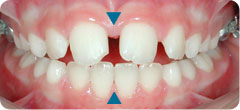

After palatal expansion, the mandible is centred and the upper and lower midlines are aligned (see blue triangles). The mandible can now grow normally.

After